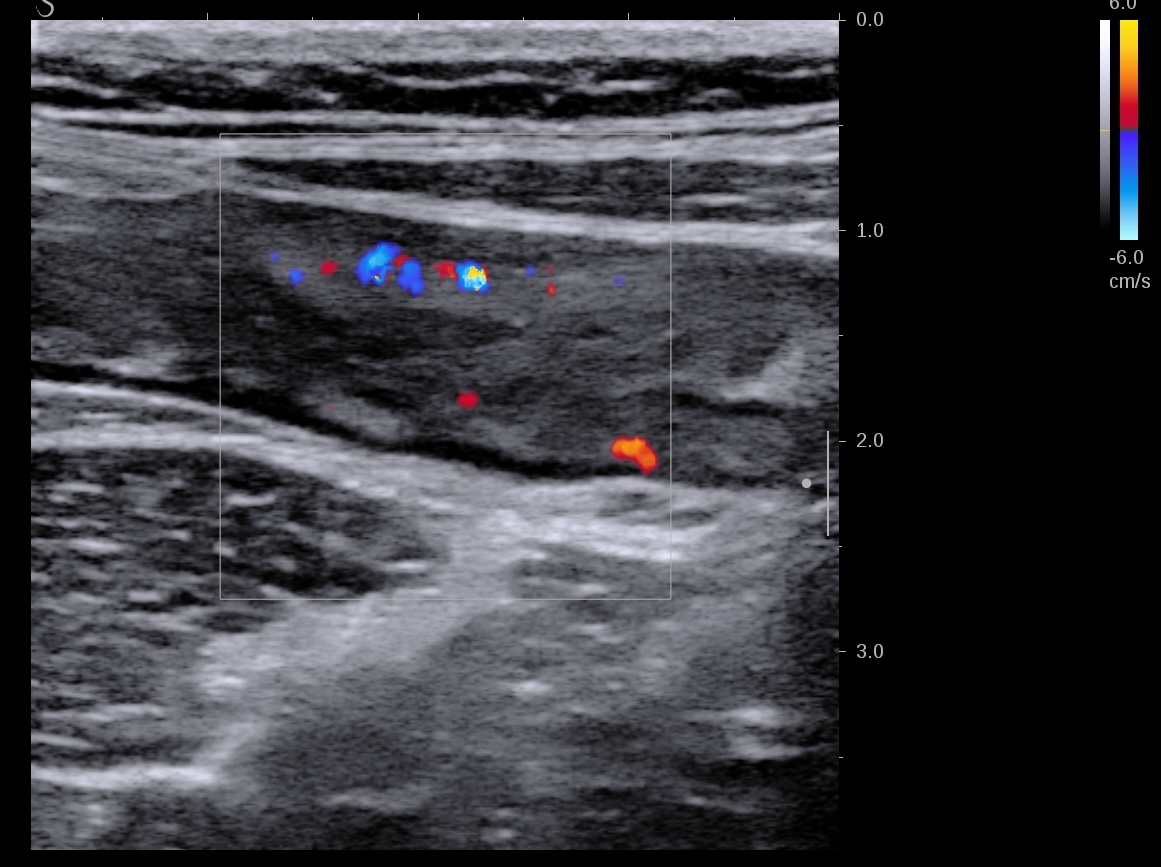

Epaississement considérable par endroit (10 ou 11 mm), disparition totale de la structure en couches, déformation de la surface avec ulcérations, déformation des contours, infiltration de la graisse, hyperactivité Doppler

Le Score de Milan (MUC) est à 17.4

Les images échographiques correspondent parfaitement aux images endoscopiques, et sont finalement beaucoup plus précises que les images scanographiques.